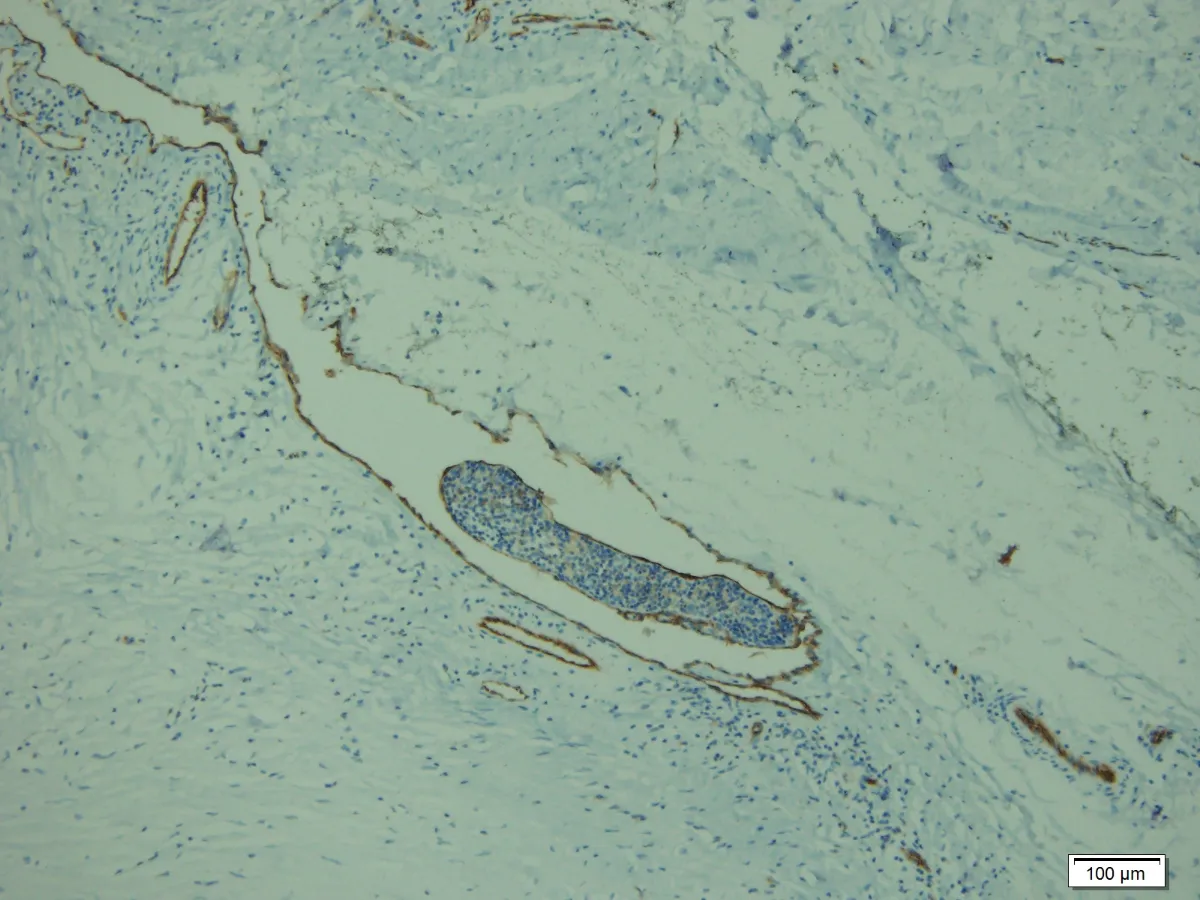

10- Invasión vascular

- Las células tumorales son difusamente positivas para pancitoqueratina y CK7. EMA y CEA tiñen el componente epitelial. Mientras, p63 y podoplanina (D2-40) tiñen las células mioepiteliales. (PMID: 23026931)

- Las tasas de recurrencia local y metástasis son del 26 al 50%, respectivamente, según algunos autores. También, se ha reportado invasión linfovascular. (PMID: 23026931)